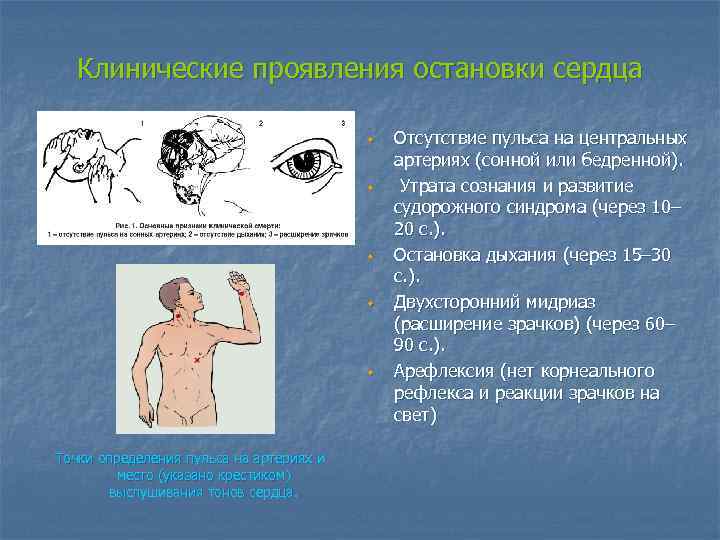

Клинические проявления остановки сердца w w w Точки определения пульса на артериях и место (указано крестиком) выслушивания тонов сердца. Отсутствие пульса на центральных артериях (сонной или бедренной). Утрата сознания и развитие судорожного синдрома (через 10– 20 с. ). Остановка дыхания (через 15– 30 с. ). Двухсторонний мидриаз (расширение зрачков) (через 60– 90 с. ). Арефлексия (нет корнеального рефлекса и реакции зрачков на свет)